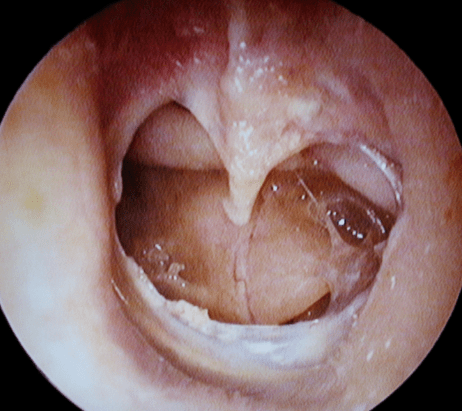

5. Eardrum Perforation or Trauma

Pain may be sudden, sharp, or associated with discharge after injury or loud noise.

- Myringotomy for chronic middle ear fluid